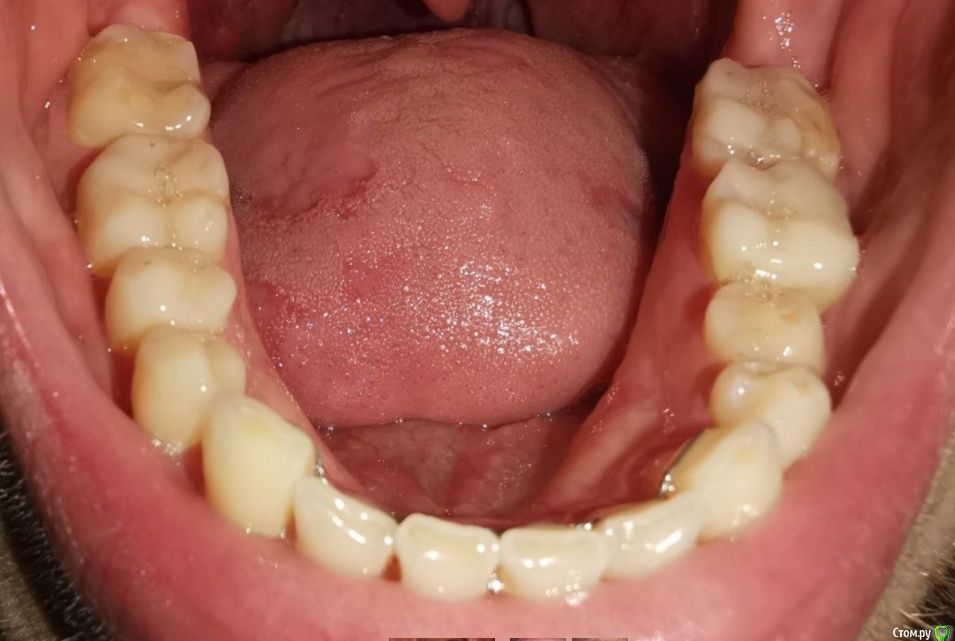

Мне 30 лет, лет 5 назад стоматолог-терапевт заметил излишнюю стираемость, была долгая эпопея с ортодонтическим лечением и вот наконец в прошлом месяце сняли брекеты и теперь настало время ортопедического.

Врач, который работает в паре с ортодонтом настаивает на полном протезировании (спереди виниры emax, сзади накладки так же из керамики). Со слов врача после диагностики сустава стало понятно, что чем выше поднимем прикус тем лучше, так должен уйти бруксизм, который сейчас присутствует.

Альтернативное мнение, которые я получил, что можно сделать накладки только на 5/6/7 со всех сторон, восстановить клыки композитом для "клыкового ведения" и пока все - полное протезирование всегда успеется. Может быть немного пожертвовав высотой прикуса.

По мнению первого врача, если делать только жевательные зубы выводя на нужную высоту прикуса, то передние зубы не сомкнутся и это нехорошо.

п.с. На некоторых зубых есть временные накладки, которые делали на время отродонтического лечения.